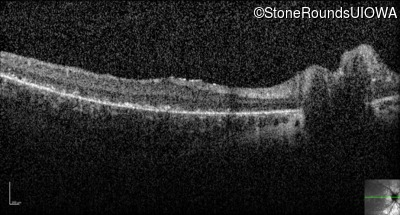

Optical Coherence Tomography - Right - 10/700 sc

Exemplar / OCT Stack